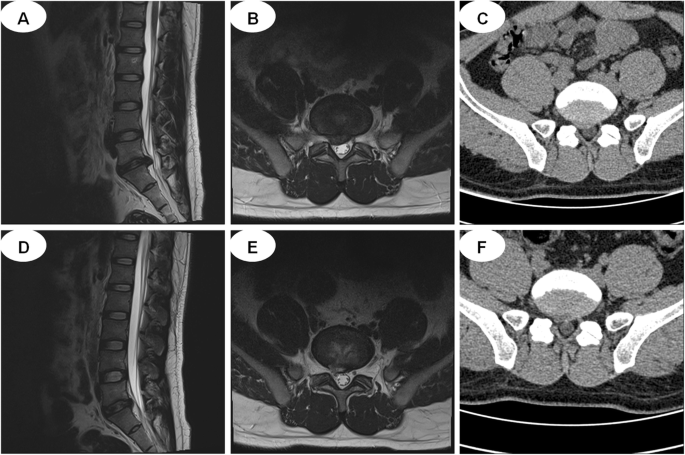

MED group: 1) Surgery was carried out under general anesthesia with the patients in the prone position. 2) A longitudinal skin incision of 20 mm was made approximately 30 mm lateral to the spinous process line. 3) A diameter was inserted towards the inter lamina space after dissection of the fascia under the guidance of C-arm. 4) Dilators were inserted sequentially, and a tubular retractor was placed to the inferior border of the lamina and the medial border of the inferior articular process. 5) Exposing the ligamentum flavum, and removing the adhering soft tissues together with part of the bony structures from the lamina and the articular process. 6) Splitting the ligamentum flavum, and exposing the compressed dural sac and nerve root that were removed carefully to decompress the nerve root. Following discectomy, the intervertebral space was washed with saline solution, and suction drainage was placed. Preoperative MRI, postoperative MRI, and X-ray images are shown in Fig. 3.